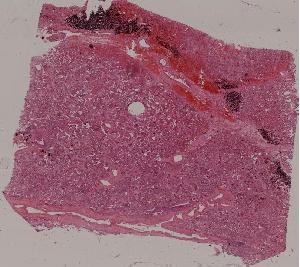

51.肺肉质变